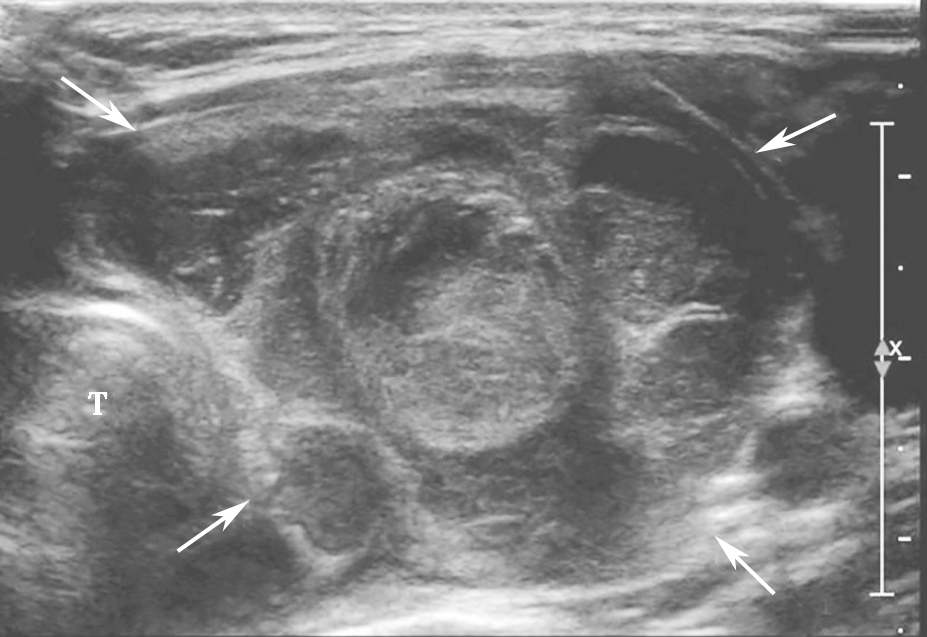

(四)桥本甲状腺炎

桥本甲状腺炎超声表现为甲状腺弥漫性增大,以前后径改变最为明显,峡部明显增厚。腺体包膜清晰完整,回声弥漫性不均减低(图2)。腺体内可见多个由淋巴组织、残余滤泡和上皮组织形成的无占位效应的低回声小结节。腺体广泛纤维化后体积可缩小。甲状腺下极附近淋巴结增大对于诊断有参考价值。

图2颈部正中横切面:甲状腺腺体回声不均匀,峡部增厚,可见多个无占位效应的低回声小结节(箭头所示),T:气管